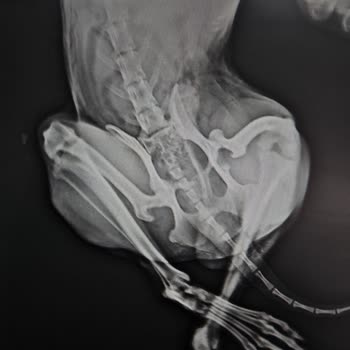

8 aylık, 2,5 kg ağırlığında Maltipoo cinsi köpeğim Bal, ön bacak kırığı nedeniyle Kurban Bayramı’nın ilk günü açık olan Beylikdüzü Petricor Veteriner Kliniği’ne götürüldü. Kırığa ek olarak eklem çıkığı olduğu söylendi, eklem bandajla sabitlendi ve kırık için pin uygulaması yapıldı. Sonrasında, 10’ar...